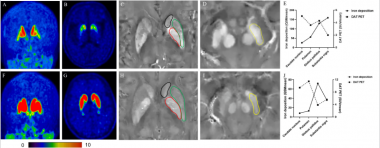

MRI兼容的高性能PET研究及医学应用——中国科学院深圳先进技术研究院研究员柳正